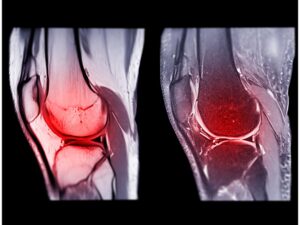

Read MoreArthritis in Knee: Symptoms, Causes and Treatment

Arthritis in Knee: Symptoms, Causes and Treatment Arthritis is a...